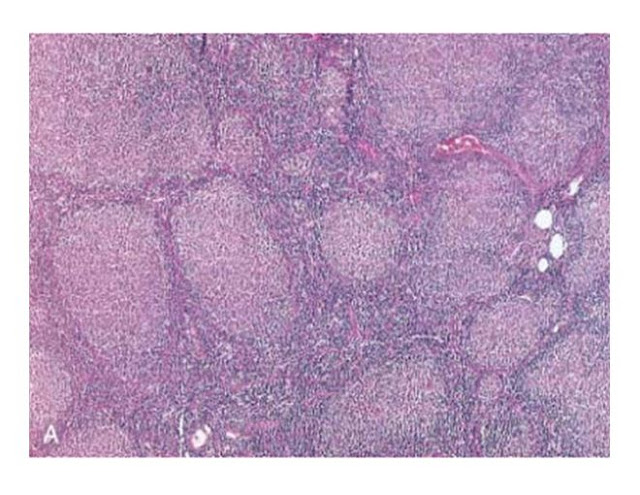

Follicular lymphoma (lymph node). A,

Nodular aggregates of lymphoma cells are present throughout lymph node.

B, At high magnification, small lymphoid

cells with

condensed chromatin and irregular or

cleaved nuclear outlines (centrocytes) are mixed with a population of larger

cells with nucleoli (centroblasts). (A, courtesy of Dr. Robert W.

McKenna, Department of Pathology,

University of Texas Southwestern Medical School, Dallas, TX.)